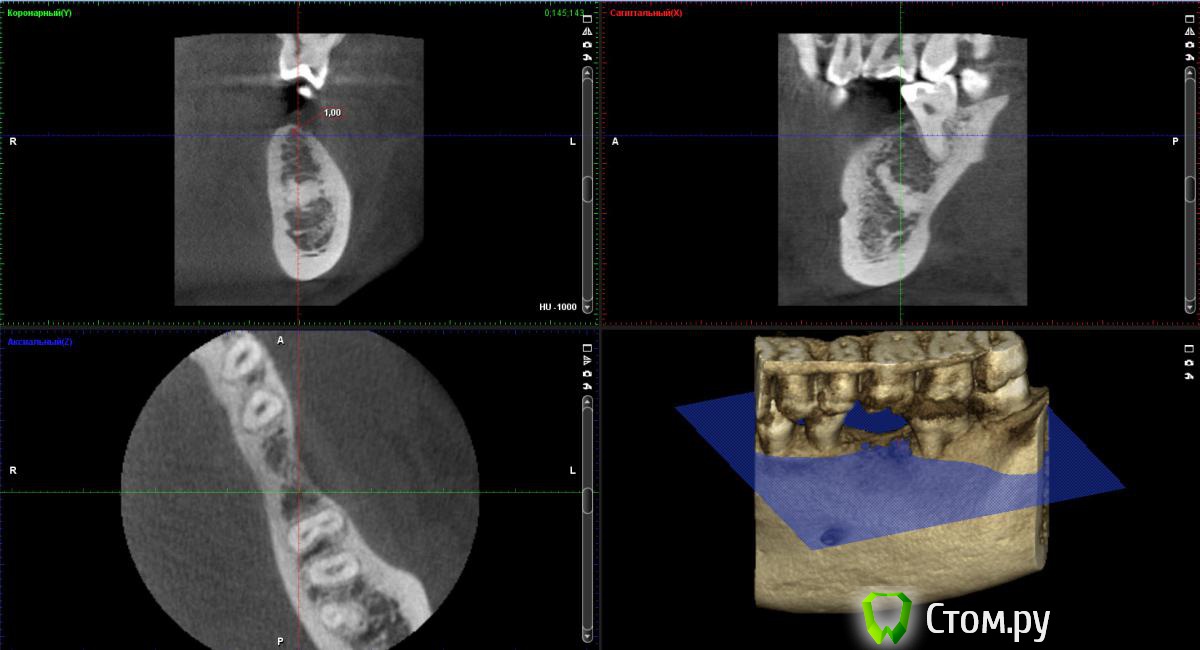

bobrdobr Опубликовано 18 февраля, 2014 Автор Поделиться Опубликовано 18 февраля, 2014 (изменено) Имплант был предложен Semados 4,1*11,5 без костной пластики. судя по фото, скорее всего нужна. От КТ нужен срез горизонтальной плоскости - вид сверху на костный гребень, на 1 мм ниже его вершины. Сейчас попробую. Прикладываю 4 снимка: на уровне гребня (как мне кажется) и на 1,2,3 и мм. ниже. Изменено 18 февраля, 2014 пользователем bobrdobr Ссылка на комментарий

Bier Опубликовано 18 февраля, 2014 Поделиться Опубликовано 18 февраля, 2014 Можно поставить, одновременно добавив немного кости и закрыть мембраной. Кость можно даже взять прямо из того места, куда будет ставиться имплантат, т.е. доп травмы не будет Ссылка на комментарий

bobrdobr Опубликовано 18 февраля, 2014 Автор Поделиться Опубликовано 18 февраля, 2014 Можно поставить, одновременно добавив немного кости и закрыть мембраной. Кость можно даже взять прямо из того места, куда будет ставиться имплантат, т.е. доп травмы не будетБольшое спасибо за мнение! Ровно такой вариант предлагал хирург 3 под винтовой имплант. Правда, он же предложил байкон Что будет, если кость не подсыпать и мембрану не ставить? Ссылка на комментарий

Bier Опубликовано 18 февраля, 2014 Поделиться Опубликовано 18 февраля, 2014 Может и ничего не будет, если широкий диаметр не выбирать и десну подсадить, а может десна немного отойдет вниз через годик-другой. Ссылка на комментарий

bobrdobr Опубликовано 18 февраля, 2014 Автор Поделиться Опубликовано 18 февраля, 2014 Все ясно, благодарю. Диаметр 4,1 мм предлагают (Semados). Нормально для жевательного зуба? Ссылка на комментарий

Bier Опубликовано 18 февраля, 2014 Поделиться Опубликовано 18 февраля, 2014 Тогда подсыпать однозначно нужно, 4,1- стандартная платформа. Лучше сюда ставить тонкую платформу. Неважно какой зуб, они держат нагрузку. Главное чтобы кость была вокруг имплантата. Ссылка на комментарий